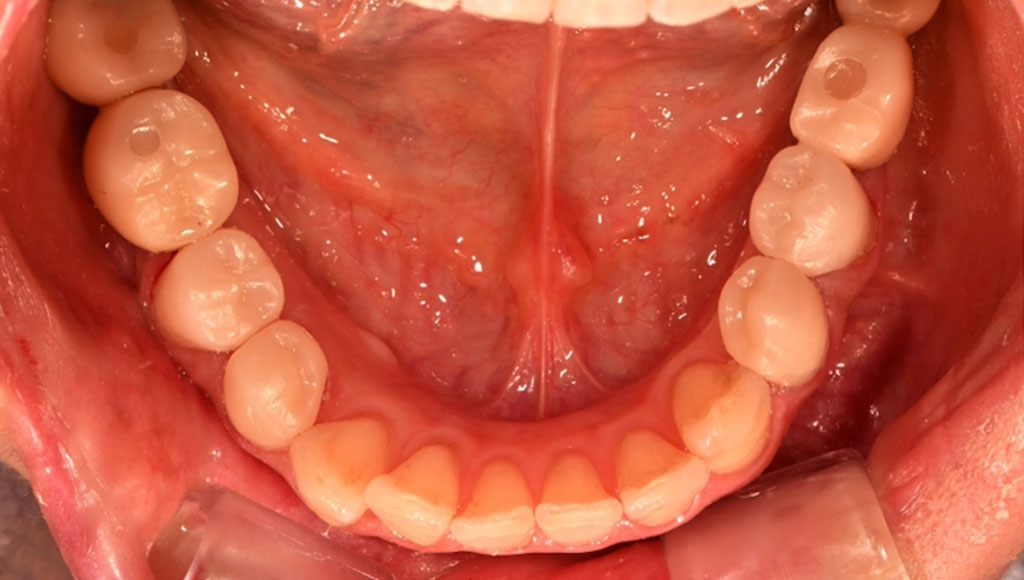

小臼歯(左下45番、右下45番)ジルコニアクラウンによる審美治療

Before1

After1

Before2

After2

患者様の主訴

50代女性。横浜市在住。左下45番、右下45番の奥歯の銀歯が見た目に気になりご来院。

診断結果

左下45番、右下45番のインレーを外し、歯の形成を行いジルコニアクラウンをセット

治療内容

ジルコニアクラウンを装着するために元のインレーを外し、歯の形成を行い光学印象(プライムスキャンによる)型取りを行いました。光学印象のデータを元に当院の院内技工室にてデジタル加工を行い、ジルコニアクラウンを作成し、セットを行いました。

治療期間

2回

治療費用

総額:440,000円(税込)

◼️内訳

ジルコニアクラウン:110,000円(税込)/1本×4本

光学印象(プライムスキャン)

リスク・副作用

補綴物の脱落・欠落、咬合違和感、色調補正